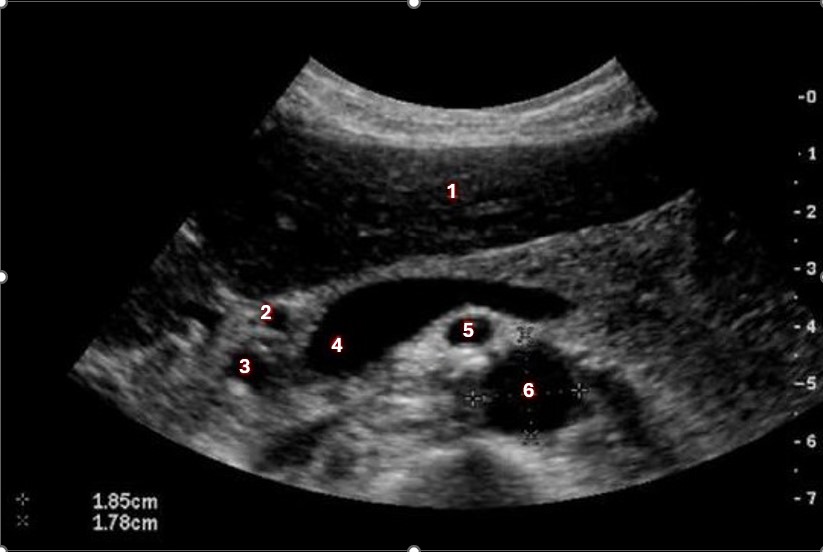

Which of the following structures is labeled number #1?

Left hepatic vein

What structure/vessel is indicated by #2?

Head of pancreas

What structure/vessel is indicated by #3?

Gastroduodenal artery

What structure/vessel is indicated by #1?

Medial branch of LPV

What structure/vessel is indicated by #6?

Superior mesenteric artery

Left portal vein

Which of the following structures is labeled #4?

Right hepatic vein

Which structure/vessel is indicated by #5?

Lateral left lobe

What structures/vessel is indicated by #5?

Tail of the pancreas

Which structure/vessel is indicated by #4?

Body of the pancreas